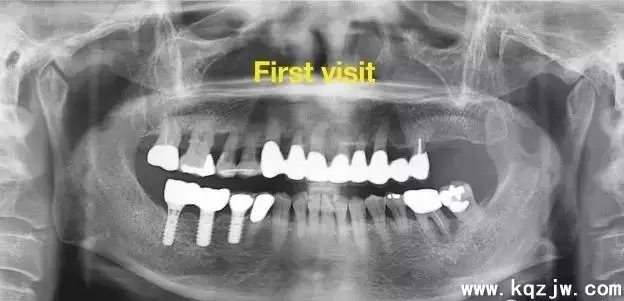

【摘要】目的:使用口腔固定技術(shù)再植固位脫落牙并觀察脫落牙保持率分析結(jié)果;方法:對16例7-10歲少年21顆脫位牙應(yīng)用口腔正畸技術(shù)即刻再植;結(jié)果:經(jīng)過1-4年的臨床觀察,患牙的保持率為100%;結(jié)論:口腔固定正畸技術(shù)能夠有效的使脫位牙再植固位

兒童牙外傷是口腔正畸兒童牙科門診的常見病,常發(fā)于上頜前部,而牙齒完全性脫位又是兒童牙外傷中較為嚴(yán)重的一種。我科自1999.9-2004.6共收治16例7-13歲21顆脫位牙,對其進(jìn)行固定正畸技術(shù)即刻再植,術(shù)后定期隨訪1-4年,患牙保持率100%。

脫位的21顆牙中:19顆無痛、無變色、無松動、根尖陰影牙周膜間隙無增大。

2顆有輕度叩痛,根尖有陰影、有輕度變色(后經(jīng)根尖誘導(dǎo)形成術(shù))、叩痛消失、根尖陰影消失,總的患牙保持率100%。